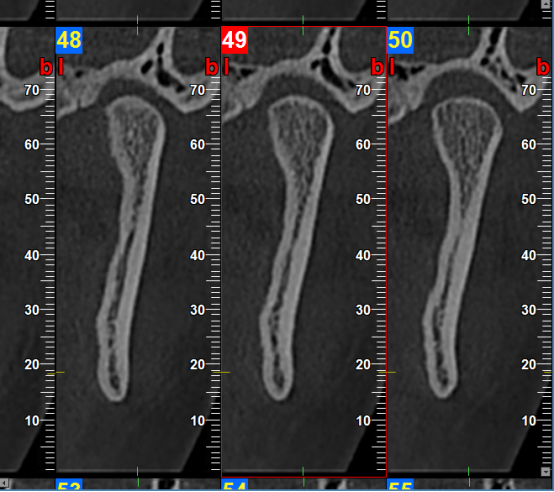

根管和牙周治疗过程中,提供牙根位置、角度、是否牙裂病变及下颌管、牙周围组织高清图像,以便于分辨治疗每个细节,做出精确诊断以及有效治疗方案。